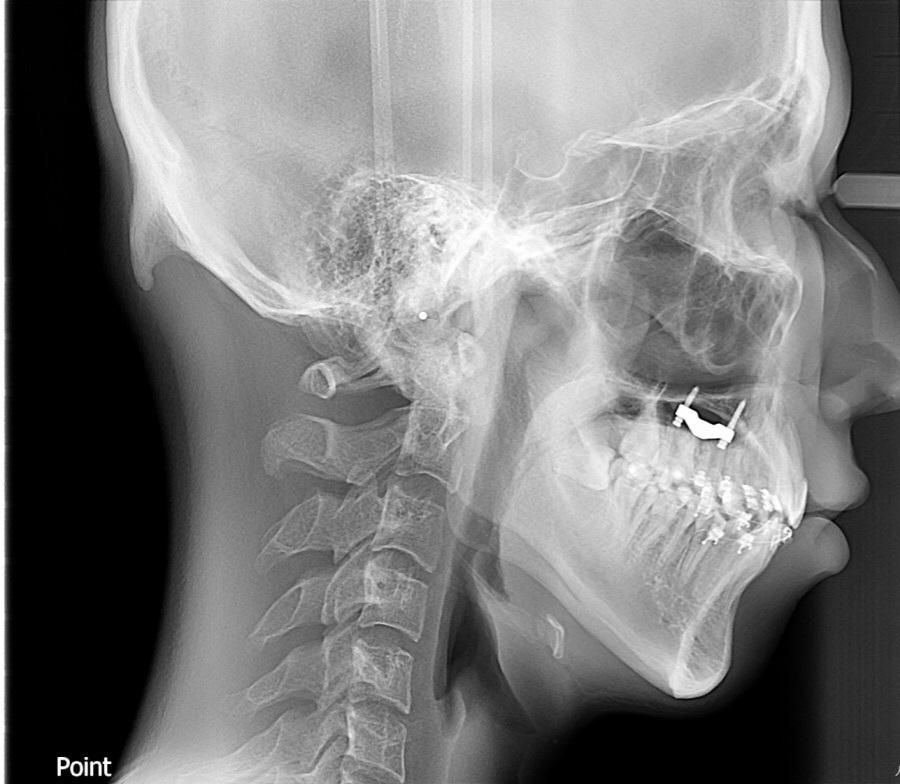

턱뼈가 길어졌는지 확인해주세요..

교정중이고marpè악궁확장장치를 남들보다 훨씬많이 100번넘게 돌렸습니다 20대초남자인데 교정전보다 턱이 길어진것같은데 엑스레이들보고 하악체부길이랑 턱뼈길이 확인해주세요 교정전사진은 턱끝이 경추4번?(몆번인지는 모름)에 도달안했으나 교정후사진은 턱끝이 경추4번?을 넘어갑니다

• 2번 째 사진

현재 사진으로는 악궁확장장치로 인한 영향을 평가할 수 없습니다. 악궁확장장치는 palatine bone을 직접적으로 관여하게 되며 이는 입천장 쪽입니다. 현재 보이는 사진에서 질문자님이 느끼시는 것은 자세 문제 때문입니다. 즉 자세에 따라서 보이는 부분이 달라질 수 있는 것이지 단순히 뼈의 위치로 판단하지 않습니다. 또한 악궁확장장치는 직접적으로 턱뼈가 길어지게 만드는 작용이 아니므로 영향이 적습니다.

상악 확장장치는 하악과는 상관없고요 하악은 실제로도 확장 자체가 잘 안됩니다. 골격적인 성장은 끝난상태에서 하악각이 시계방향으로 회전하면서 턱이 길어보이게 될 순 있습니다.